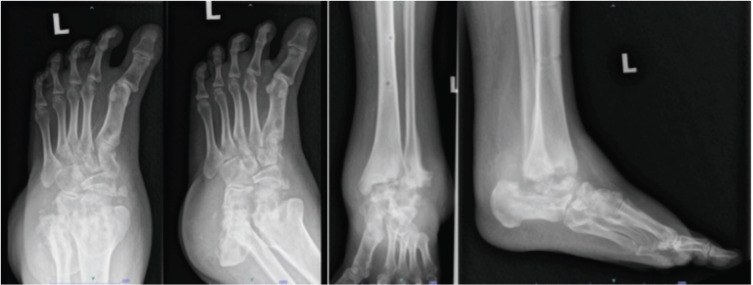

Materials and methods: All patients with active Charcot arthropathy treated at the medical centre from 1 January 2013 to 30 June 2020 were included in the study. Efficacy outcome was evaluated based on time to consolidate findings observed through radiographic examination, while safety outcome was evaluated based on the incidence of adverse event (AE) occurrence.

Results: A total of 81 patients (37 male, 44 female) diagnosed with active Charcot arthropathy were included. 64.2% of patients were at stage 1 of Charcot arthropathy whereas 35.8% were at stage 2. The mean time to consolidate for stage 1 and stage 2 was 6.50 ± 4.21 months and 3.63 ± 2.92 months respectively (p-value = 0.139). No significant association was observed between gender, ethnicity and disease stage with the consolidation time (p-value >0.05). The rate of AE incidence was 2.5%, observed in 2 patients who developed a fever during the treatment. No other serious AE was observed in the study.